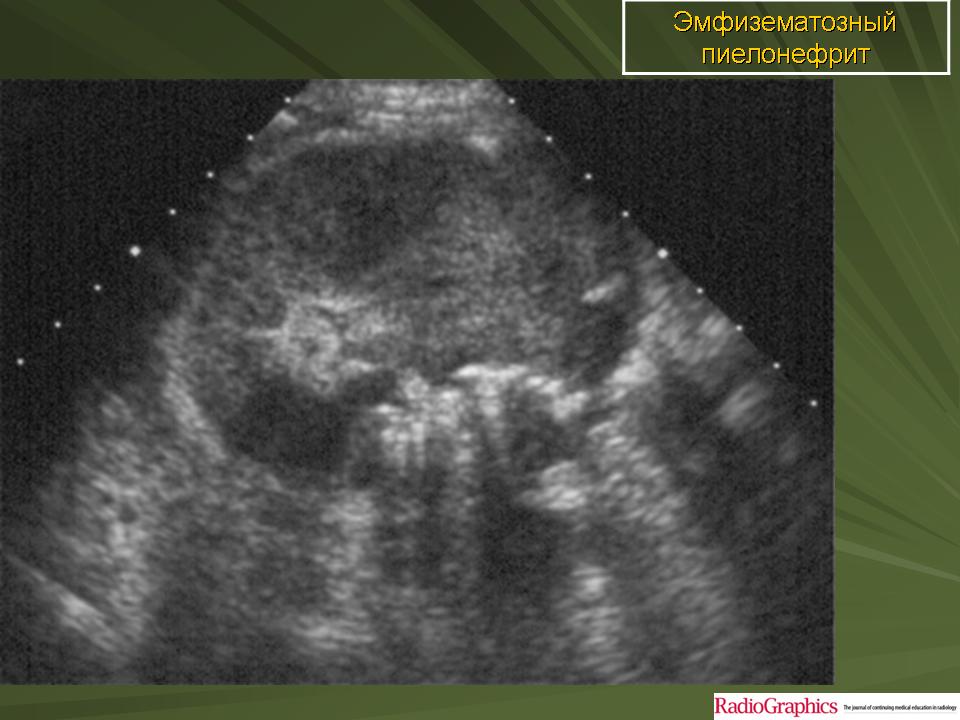

Эмфизематозный пиелонефрит

ID: 17283 Emphysematous pyelonephritis Dr Maulik S Patel - 1 Apr 2012 Emphysematous pyelonephritis

ID: 24370 Emphysematous pyelonephritis Dr Ian Bickle - 10 Aug 2013 This is a case of emphysematous pyelonephritis. This constitutes only a...